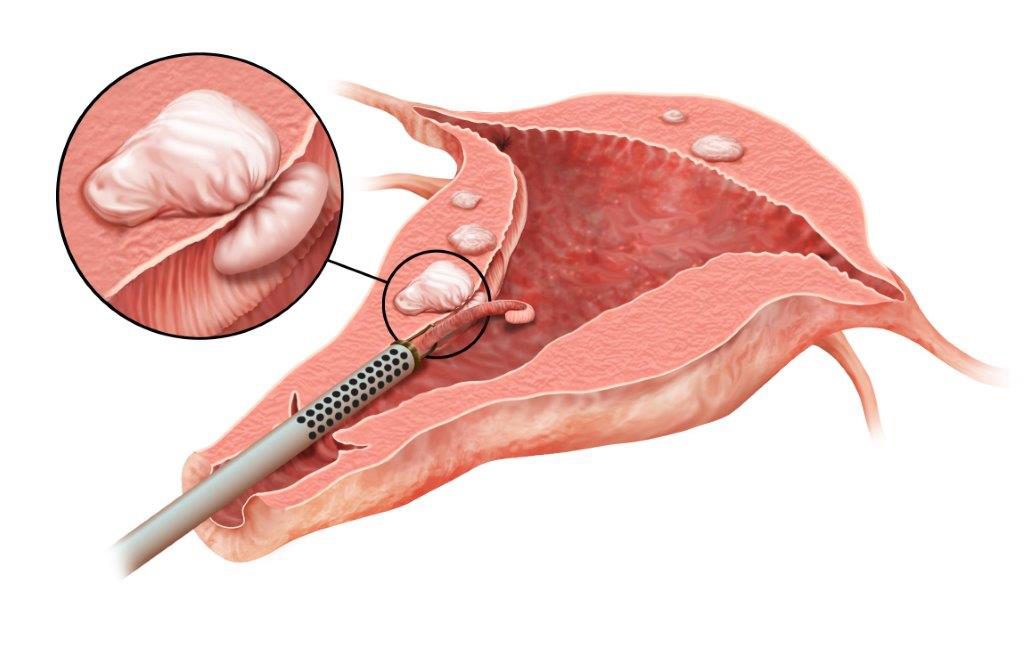

Современные методы лапаротомии и миомэктомии